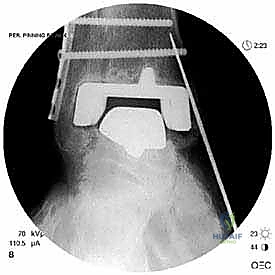

- الأشعة السينية مع تحميل الوزن (Weight-bearing X-rays): لتقييم الزوايا الميكانيكية وتحديد مدى هبوط المفصل أو وجود كسور في الكعب.

علاج هذه الكسور يتطلب مهارة فائقة من الدكتور محمد هطيف، حيث يتم استخدام تقنيات الجراحة الميكروسكوبية وتثبيت الكسور باستخدام صفائح معدنية دقيقة ومسامير (Locking Plates) دون المساس بثبات المفصل الصناعي، أو يتم دمج علاج الكسر ضمن عملية مراجعة المفصل الكلية إذا كان المفصل نفسه تالفاً.

يتم تخدير المريض (نصفياً أو كلياً) واستخدام عاصبة (Tourniquet) لتقليل النزيف. يتم تعقيم الطرف السفلي وتجهيز أجهزة الأشعة المرئية (C-arm) داخل الغرفة.

الخطوة الخامسة: تركيب المفصل الجديد أو الدمج

يتم إدخال المفصل الجديد المخصص للمراجعة، والذي يحتوي غالباً على سيقان (Stems) تدخل عميقاً في عظمة الساق وعظمة الكاحل لضمان الثبات الميكانيكي. في حال وجود كسور في الكعب، يتم تثبيتها في هذه المرحلة.